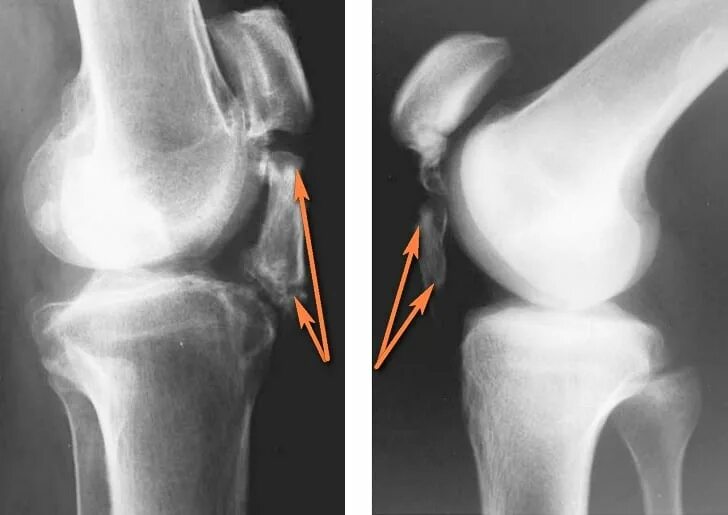

Лигаментоз коленного сустава рентген. лигаментоз тазобедренного сустава рентген. обызвествление в мягких тканях коленного сустава рентген. тендиноз тазобедренного сустава рентген.

Лигаментоз коленного сустава рентген. хондроматоз голеностопного сустава. лигаментоз надколенника. лигаментоз надколенника рентген.

Лигаментоз коленного сустава. лигаментоз связок коленного сустава. лигаментоз тазобедренного сустава. лигаментоз крестообразных связок рентген.

Лигаментоз коленного сустава рентген. лигаментоз надколенника рентген. рентген коленного сустава пкс. повреждение связок коленного сустава рентген.

Лигаментоз коленного сустава рентген. оссифицирующий лигаментоз коленного сустава. лигаментоз связок коленного сустава. лигаментоз надколенника рентген.

Лигаментоз коленного сустава рентген. тендиноз коленного сустава рентген. пороз коленного сустава рентген. лигаментоз коленного сустава рентгенологическая картина.